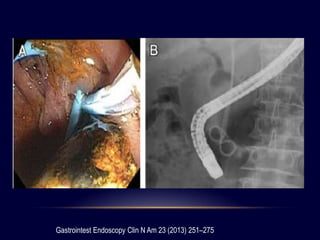

COLOCACIÓN DE STENT BILIAR

• Inicialmente reservada para pacientes ancianos

y con complicaciones serias (Bergman)

• Complicación mas importante 16% la infección

• Cálculos grandes (>2cm), múltiples (>3)

• Adición de UDCA

Gastrointest Endoscopy Clin N Am 23 (2013) 251–275

• Reducción del tamaño en 60%

• Posiblemente por irritación mecánica

• Estudio 28 pacientes geriátricos

• Stent + UDCA: reducción significativa en el tamaño del

cálculo

• Posteriormente la remoción endoscópica se pudo

hacer en 26 pacientes

Am J Gastroenterol 2009; 104: 2418-2421

• Mayor confort comparado con el drenaje nasobiliar

• Tasa de utilidad del 44 – 92%

• Reducción del tamaño del cálculo

DESVENTAJAS

Colangitis:

3,5 – 40% de pacientes

16 semanas

Aumenta con el tiempo

Oclusión:

No se conoce la causa exacta

Reflujo biliar es una hipótesis

Migración del stent

The surgeon 1 0 ( 2 0 1 2 ) 2 1 1 - 2 1 7